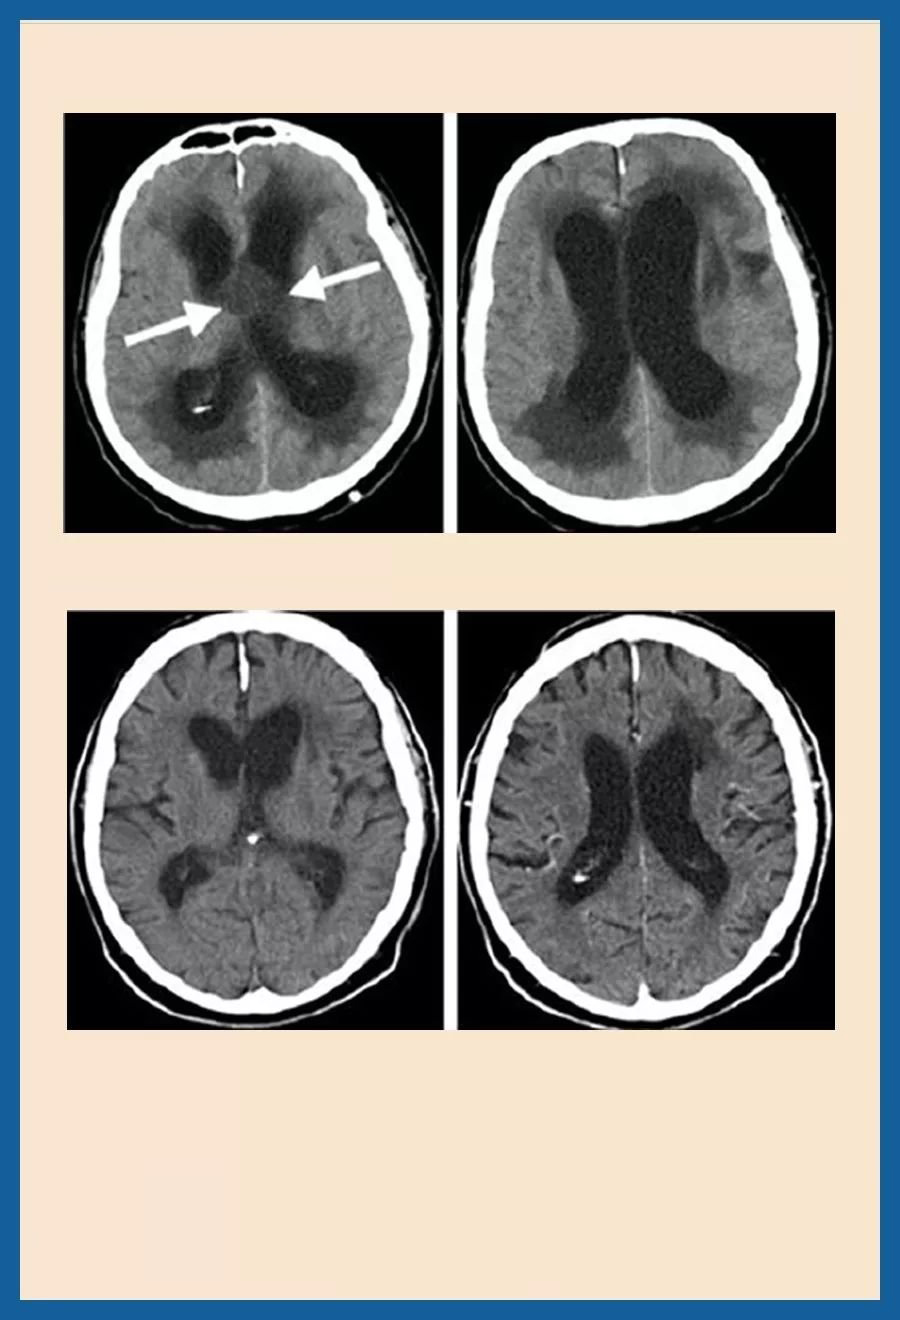

术前CT:显示大的囊性颅咽管瘤,伴有闭塞性脑积水。三脑室中囊性肿瘤的脑室系统大大增大。

手术方法:小钻孔神经内镜下肿瘤微创切除术

术后情况:肿瘤被完全切除。脑积液循环恢复正常,术后患者恢复地很好,记忆障碍消退,垂体功能保留。